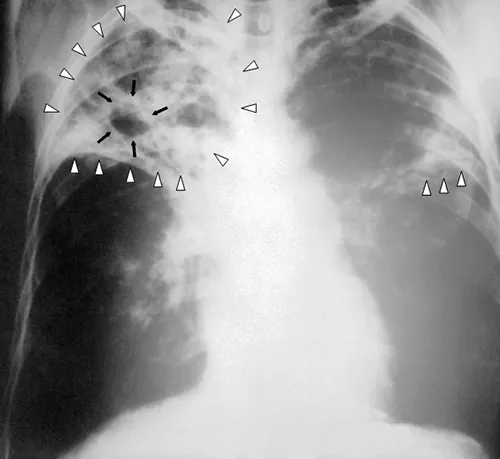

When Marsha finally went to the doctor’s office, the physician listened to her breathing through a stethoscope. He heard some crepitation (a crackling sound) in her lungs, so he ordered a chest radiograph and asked the nurse to collect a sputum sample for microbiological evaluation and cytology. The radiologic evaluation found cavities, opacities, and a particular pattern of distribution of abnormal material (Figure 4.6).

• What are some possible diseases that could be responsible for Marsha’s radiograph results?

An X-ray showing ribs and other structures as white and the lungs as black. Light white webbings in the lungs are highlighted with white triangles. A dark region in this white webbing is outlined with black arrows.

Figure 4.6 This anteroposterior radiograph shows the presence of bilateral pulmonary infiltrate (white triangles) and “caving formation” (black arrows) present in the right apical region. (credit: Centers for Disease Control and Prevention)